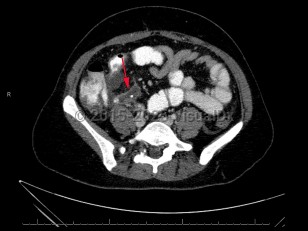

Acute appendicitis is an acute inflammatory condition of the appendix.

Appendicitis results from an obstruction of the appendiceal orifice, which can be caused by a fecalith, lymphoid hyperplasia, infection, calculi, or malignancy. Lymphoid hyperplasia is a more common etiology in younger pediatric patients. Rarely, appendicitis can be caused by infection with the parasitic worm Enterobius vermicularis.

Inflammation begins within the appendiceal lumen and extends through the endothelial wall, leading to focal ischemia, tissue necrosis, and, in some instances, perforation. Perforation can lead to complications including generalized peritonitis and abscess formation.